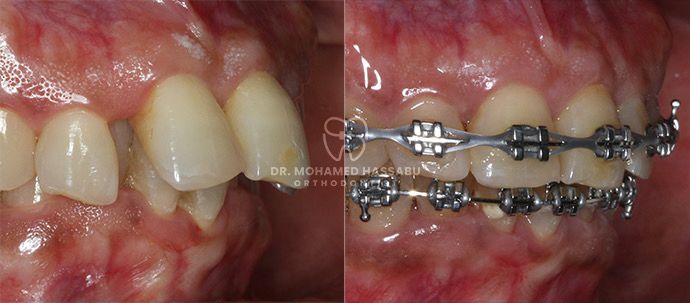

التقويم المعدني عبارة عن أدوات أسنان خاصة مصنوعة من الفولاذ المقاوم للصدأ تساعد في إصلاح الأسنان التي لا يتم محاذاتها بشكل صحيح. تحتوي هذه التقويمات على أقواس معدنية تلتصق بالأسنان وأسلاك رفيعة تعمل على تحريك الأسنان بلطف إلى الأماكن الصحيحة مع مرور الوقت. من خلال ارتداء هذا التقويم، تصبح الأسنان المزدحمة أو الملتوية مستقيمة تدريجيًا، مما يخلق ابتسامة جميلة لك ولطفلك.

لقد كانت التقويمات المعدنية حلاً موثوقًا ومثبتًا لتقويم الأسنان لأجيال عديدة. إنها فعالة للغاية في تصحيح مشاكل الأسنان المختلفة، بما في ذلك الأسنان المزدحمة، والفجوات، والعضة العلوية، والعضة السفلية. من خلال الضغط بلطف على الأسنان مع مرور الوقت، تقوم التقويمات المعدنية بنقلها تدريجياً إلى مواقعها الصحيحة، مما يخلق ابتسامة متناغمة ومتماسكة.

تركيب التقويمات المعدنية:

بفضل الدقة والعناية، سيقوم أخصائيو تقويم الأسنان الكبار لدينا بوضع التقويمات المعدنية بلطف على الأسنان، مما يضمن ملاءمة مريحة.

نقوم بجدولة مواعيد متابعة منتظمة لمراقبة التقدم وإجراء التعديلات اللازمة على التقويمات للحصول على أفضل النتائج.